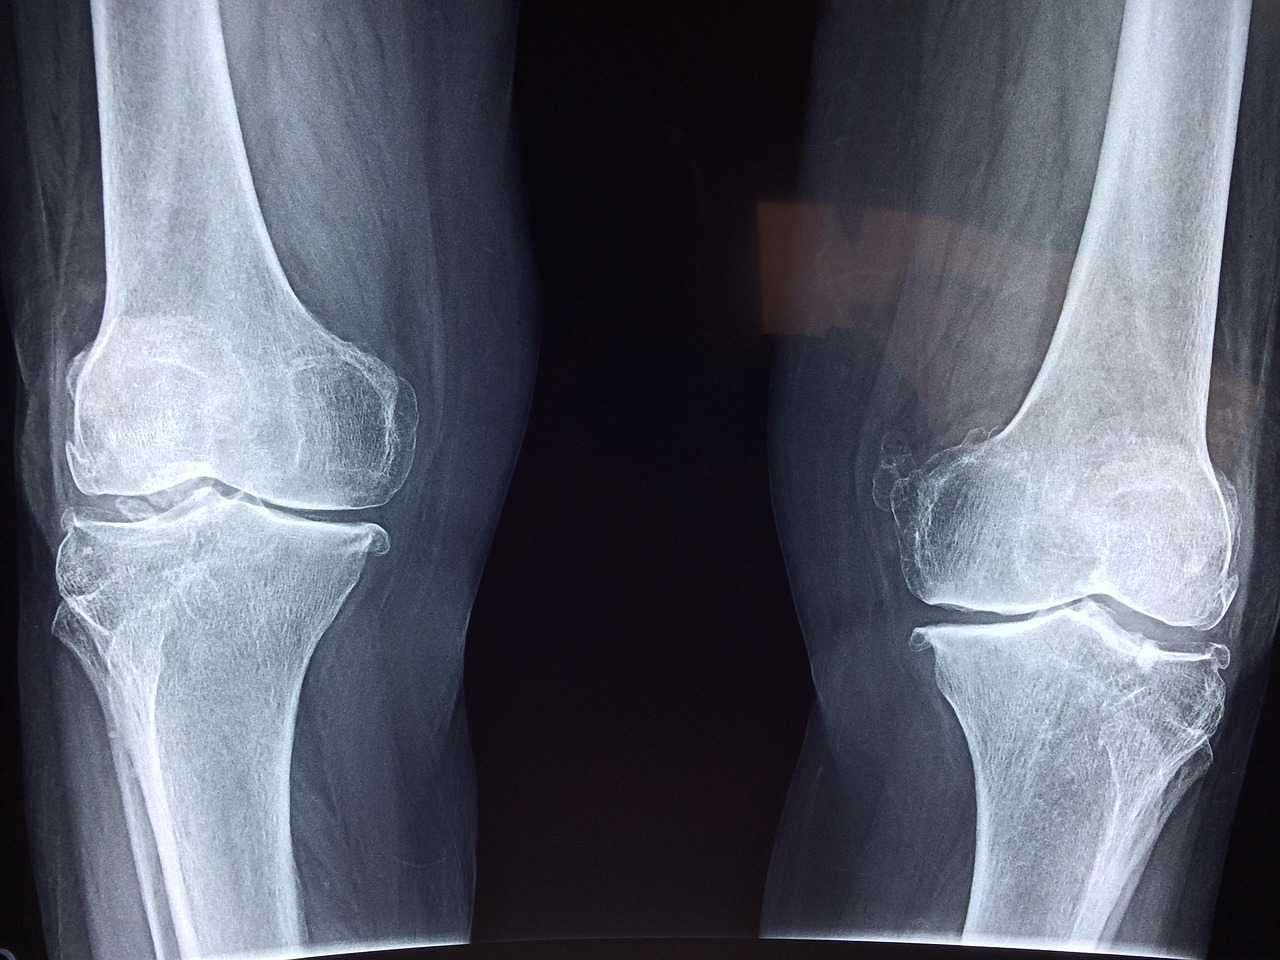

Many believe that running is detrimental to knee health, yet recent studies reveal different insights. Renowned orthopedic specialists argue that running, when performed correctly, does not inherently damage the knees. Rather, it often strengthens them. Regular runners generally have healthier joints than non-runners. The key is proper technique, which minimizes excessive strain. Experts emphasize the importance of warm-ups and appropriate footwear to prevent injury. Moreover, the concept of “runner’s knee” is often misunderstood. It is rarely due to the act of running itself but is often linked to pre-existing conditions or improper form. Studies indicate that recreational runners may actually reduce the risk of osteoarthritis compared to sedentary individuals. This has been corroborated by various health organizations, which encourage running as a beneficial activity. Moreover, those who incorporate strength training and flexibility exercises can potentially enhance their knee stability. Nutrition also plays a pivotal role in joint health. A balanced diet can help maintain cartilage health. Incorporating anti-inflammatory foods can further support the knee joints during any physical activity, including running.

In addition to proper technique, experts recommend listening to your body when engaging in running. This often helps identify issues early and mitigates the risks of injury over time. Another common misconception is that all running forms are harmful. However, variations in running surfaces can impact overall knee health. Studies indicate that softer surfaces, like grass or tracks, can significantly reduce joint impact compared to harder surfaces, like concrete. Alternating running surfaces could be beneficial. Runners should consider varying their routes to avoid repetitive stress on their knees. They may strengthen different muscle groups necessary for supporting the knee structure during their runs. Furthermore, recent analyses of elite athletes show that those who engage in diverse training methods experience fewer joint issues over time. Incorporating cross-training methods can enhance overall performance while safeguarding the knees. This approach can include cycling or swimming, which are low-impact alternatives to running. These activities further build strength and cardiovascular fitness without overwhelming the knees. The essence of maintaining knee health ultimately lies in understanding one’s limits and ensuring a comprehensive physical regimen.

Understanding Knee Health Through Research

Research reveals that running can actually be beneficial for joint health when combined with a proper understanding of biomechanics. Recent studies also emphasize the importance of muscle strengthening to support knee joint health. Engaging in exercises that target the quadriceps, hamstrings, and calves not only bolsters muscular endurance but also enhances joint stability. Experts recommend integrating these specific strength-building routines into a regular workout regimen for runners. Moreover, leading sports medicine experts have documented that running helps increase bone density, which positively impacts overall joint function. In fact, higher bone density can lead to a reduced risk of fractures and joint deterioration as one ages. This finding is significant, especially for those concerned about long-term joint health from running. Additionally, research indicates that new runners should gradually increase their distance and pace, allowing their bodies to adapt without undue strain. Engaging in a careful ramp-up program is essential. Such planning is crucial for minimizing injury risks. Ultimately, the perspective on running, once seen as harmful, now increasingly recognizes its capacity to contribute positively to knee health when performed with care and caution.

In light of the evolving understanding of running and knee health, it’s essential to dismantle fitness myths surrounding this popular activity. While misconceptions persist, the net effects of running on knee health are predominantly positive. Many beginners express concerns about possible injuries or osteoarthritis related to running. However, data from various studies indicate that a well-structured running program encourages overall joint longevity. It is critical to approach fitness within the appropriate context, considering personal health histories and listening to expert advice. The role of recovery in maintaining knee health cannot be overstated either. Adequate resting and recovery periods between runs are essential for muscle and joint repair. Overtraining without sufficient rest increases the risk of injuries and stress. Moreover, consulting a physician or physical therapist for individualized assessments can further aid runners in understanding their risks. They can provide tailored programs to enhance running safety and efficiency. Furthermore, an active lifestyle goes hand in hand with overall well-being. Knowing the proper techniques, crossing the element of strength conditioning into routines, and emphasizing recovery strategies transforms running into a joint-friendly exercise.